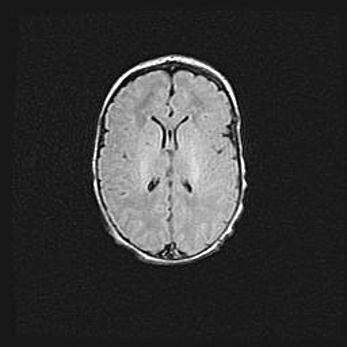

Церебральная ишемия II.

Возраст: 5 дней

Вес: 3400 г

Пол: женский

Окружность головы: 35 см

Срок гестации: 39 недель

Церебральная ишемия – это заболевание, характеризующееся недостаточностью (гипоксией) либо полным прекращением (аноксией) снабжения мозга кислородом по причине закупорки одного или нескольких сосудов. Это приводит к  что метаболическим расстройствам различной степени тяжести в тканях головного мозга, развитию коагуляционных некрозов и гибели нейронов.